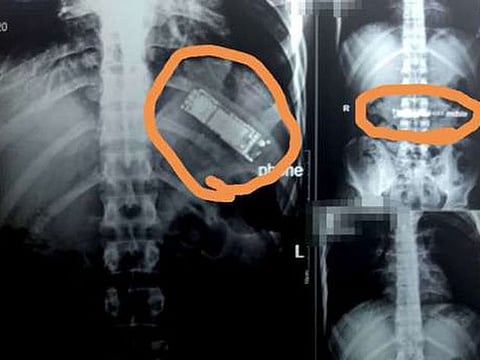

The gadget was detected in the 28-year-old man’s stomach after he underwent an ultrasound in a state hospital in the province of Benha, north of Cairo, private newspaper Al Watan said.

Dr Mohammed Al Jazar, a consultant of pulmonary tumours and heart surgeon, said the ultrasound showed the presence of the mobile inside the man’s stomach.